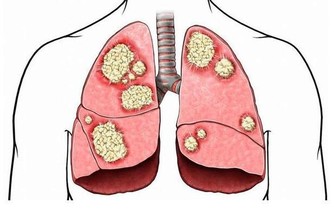

2. 它能幫你防病

在檸檬等柑橘類水果中富含的維生素C,可以增強你的免疫系統。

不僅如此,檸檬水還有助於預防感染,

它所含的植物營養素具有抗氧化特性,可以幫助保護身體免受疾病的侵害。

有助於保護細胞免受自由基的侵害,這甚至可以幫助我們預防心血管疾病和癌症。